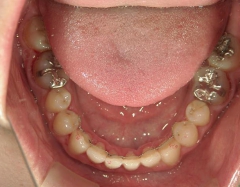

矯正歯科 治療前 急速拡大装置で上顎を広げた後、ワイヤーへ移行 非抜歯

矯正_灰色.pngno.31_7964_治療前_下.JPG矯正_灰色.png